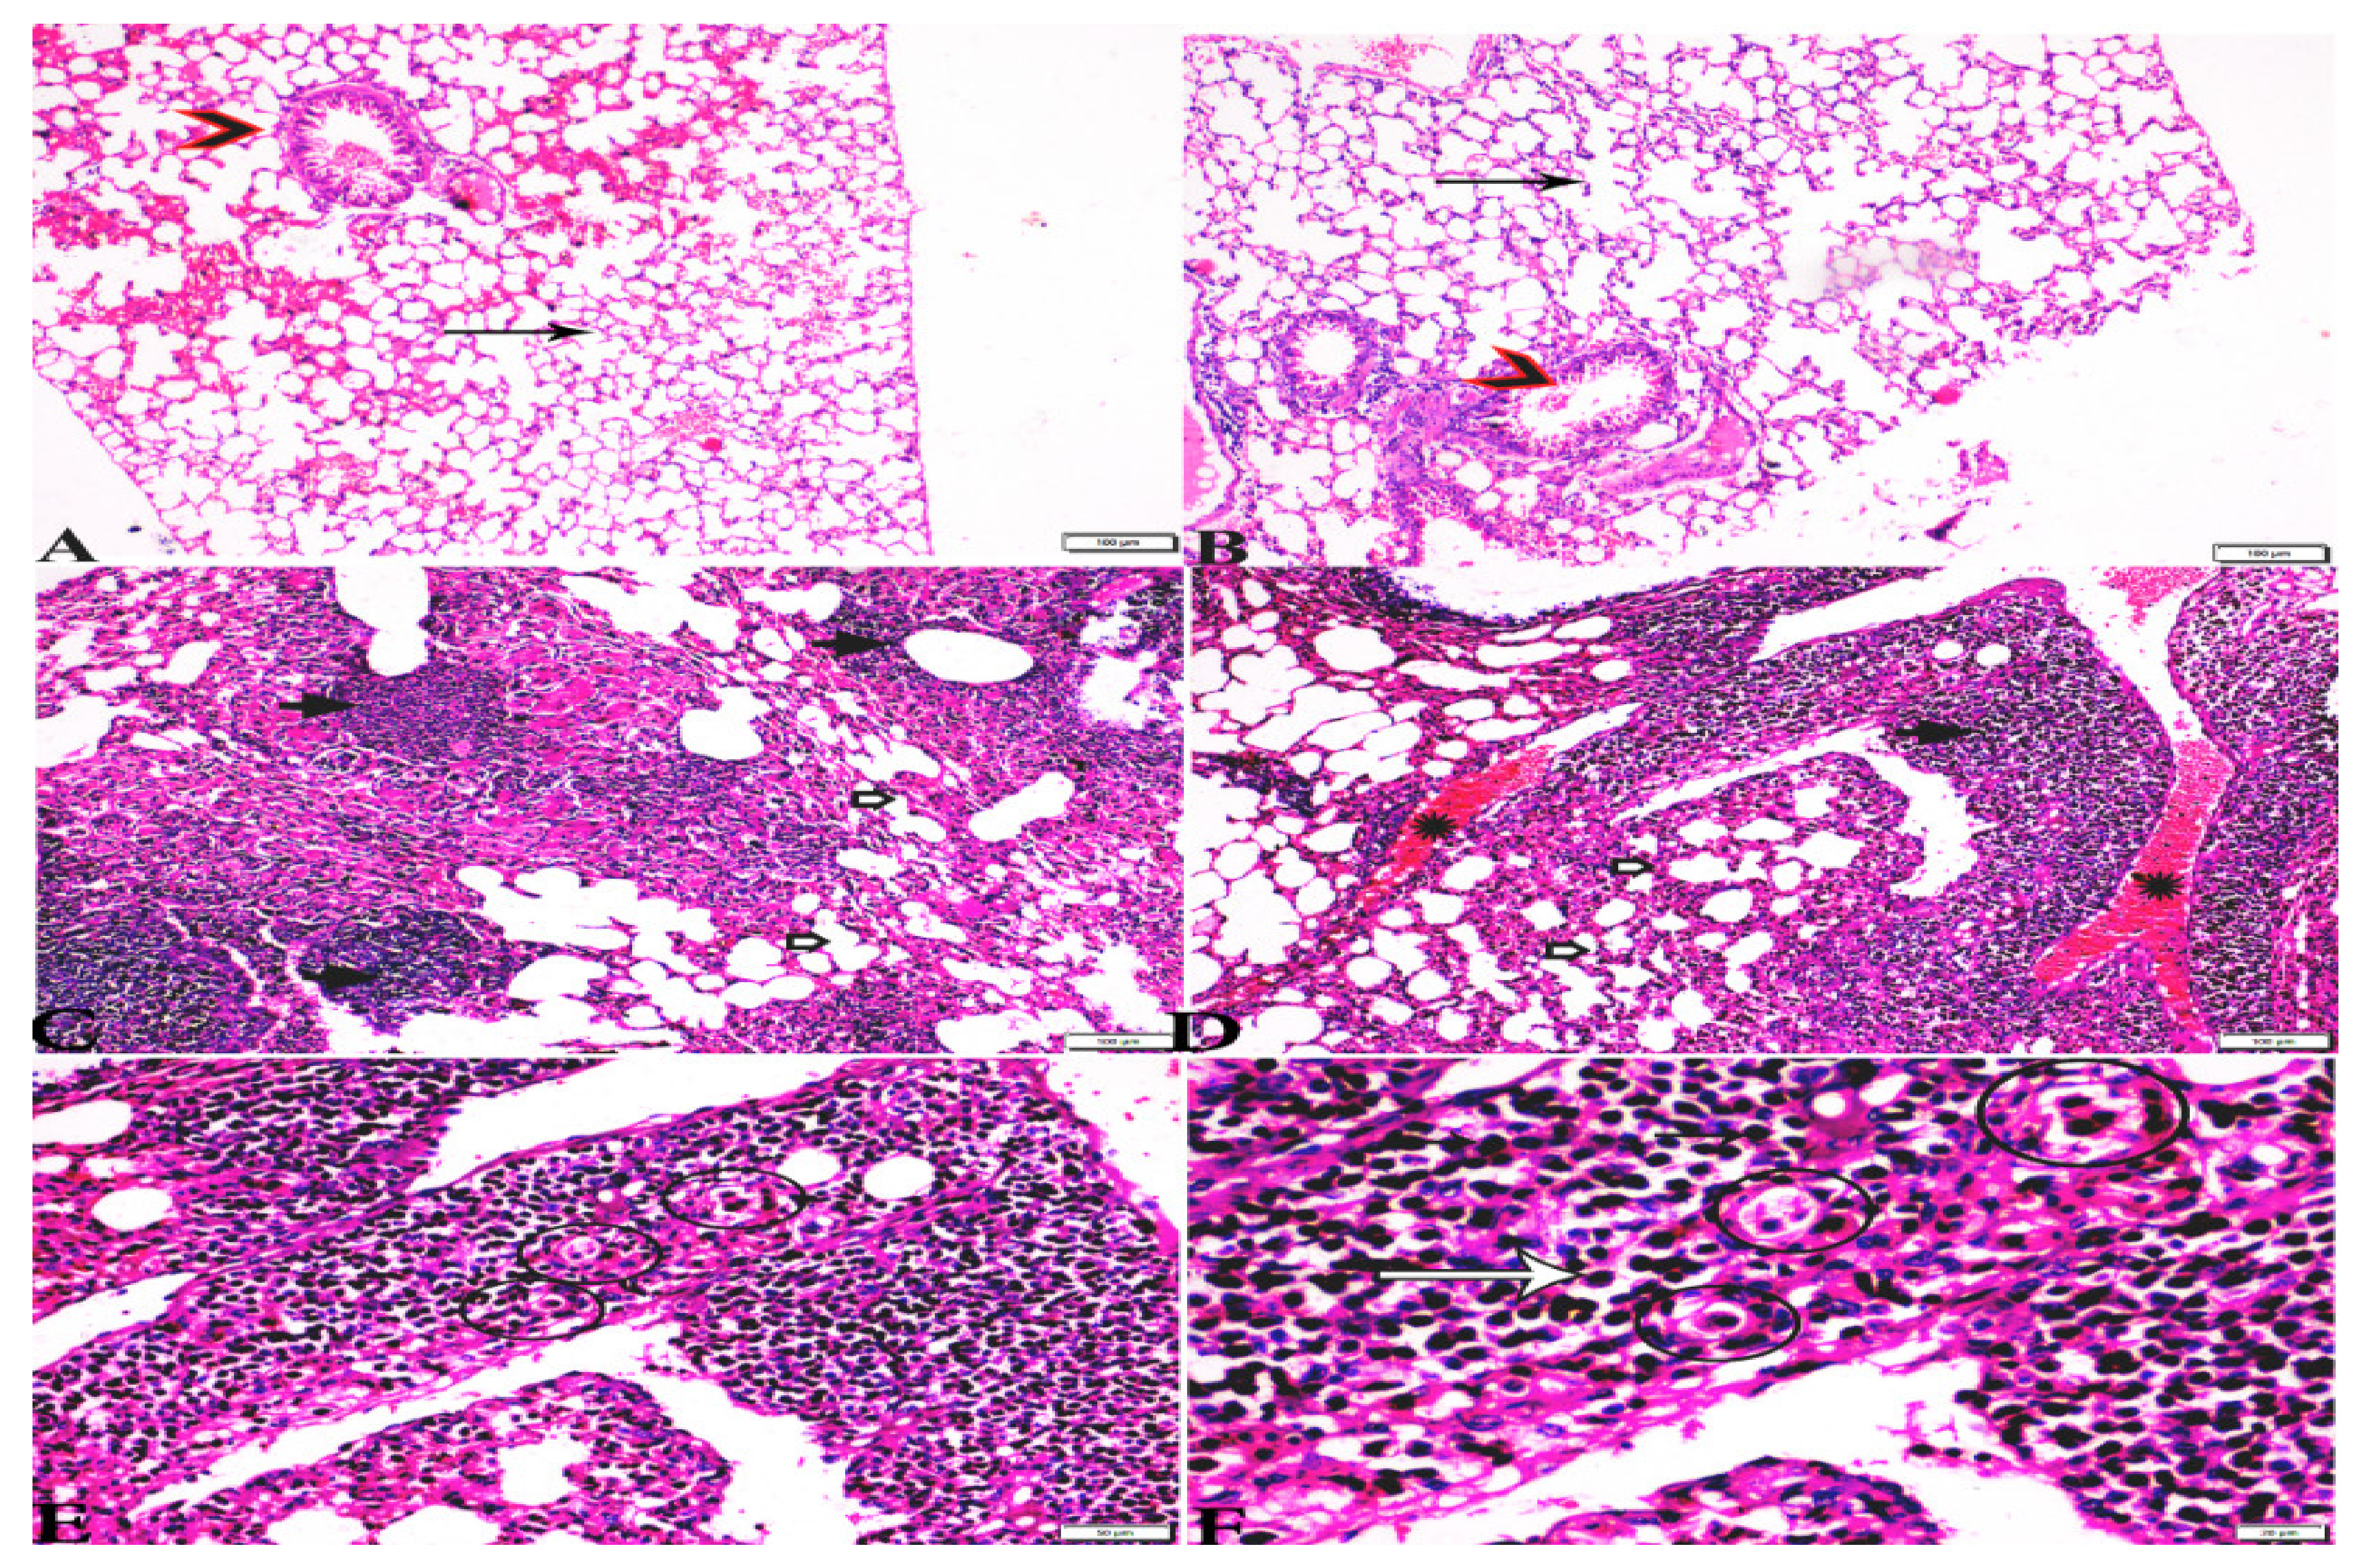

Figure 7.

Photomicrograph of H&E-stained lung tissue sections from mice in the experimental groups: (A,B): lung tissue sections from the negative control group (G1) showing: normal bronchiolar structure (arrow heads), normal alveolar tissue (arrows). (C–F): Lung tissue sections from the T. gondii-infected positive group (G2): (C,D): collapsed alveoli (white arrows), multiple focal lymphoid hyperplasia (black arrows), and severe vascular congestion (stars). (E,F): Multiple tissue cysts containing bradyzoites (circles) and multiple diffuse bradyzoites (arrows). The scale bar is provided below each image.

Figure 8.

Photomicrograph of H&E-stained lung tissue sections from T. gondii-infected animals treated with propolis (G3) showing: (A): alveolar emphysema (arrows), interstitial hemorrhage (stars), and (B) infestation with multiple tissue cysts (arrows). The scale bar is provided below each image.

Figure 9.

Photomicrograph of H&E-stained lung tissue sections from mice in the experimental groups: (A,B): lung tissue sections from T. gondii-infected mice treated with wheat germ oil (G4) showing: normal bronchiolar structure (arrowheads), congested blood vessel (stars), hemorrhage (H), and collapsed alveoli (arrows). (C,D): Lung tissue sections from the group treated with the combination of propolis and wheat germ oil (G5) showing: normal alveolar tissue (arrows), normal bronchiolar structure (arrowheads), and vascular congestion (stars). The scale bar is provided below each image.

Microscopic examination of lung tissues obtained from the negative control group (G1) (Figure 7A,B) revealed a normal bronchiolar structure and normal alveolar tissue. In contrast, lung tissue obtained from the positive control group (G2) showed severe damage, congested blood vessels, collapsed alveoli, multiple focal lymphoid hyperplasia, the presence of multiple tissue cysts containing bradyzoites, and multiple diffuse bradyzoites in the infected alveolar tissue (Figure 7C–F). Lung tissue sections obtained from infected animals treated with propolis (G3) exhibited moderate damage, alveolar emphysema, interstitial hemorrhage, infestation with multiple bradyzoites, and multiple tachyzoites (Figure 8A,B), while normal bronchiolar structure, mild damage, congested blood vessels, hemorrhage, and collapsed alveoli were observed in lung tissue specimens from animals treated with WGO (G4) (Figure 9A,B). Lung tissue from the G5 group showed normal histology and bronchiolar structure, normal alveolar tissue, and normal peribranchial lymphoid cellular structure (Figure 9C,D). Based on histopathology scoring (Figure 10), the severity of parasitic tissue cyst number, interstitial hemorrhage, blood vessel congestion, and bronchiolar epithelium structure were significantly improved (p ≤ 0.05) in all experimental treatment groups (G3, G4, and G5) compared with the positive control group (G2).